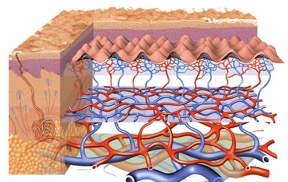

3. Sistem Integumentari

Bagi pengamal modaliti bekam khususnya, mengetahui struktur kulit dan mekanisma kerja sel dan tisu yang membentuk kulit akan dapat meningkatkan lagi kefahaman terhadap amalan bekam itu sendiri. Digandingkan dengan kefahaman pada sistem peredaan darah dan sistem imuniti, sistem integumentari ini akan melengkapkan kefahaman terhadap mekanisma kerja amalan bekam itu sendiri dalam memilih pelbagai titik bekam secara ilmiah dan tidak hanya dengan “taqlid buta” atau meniru gambar rajah atau poster titik bekam secara buta dan melulu.